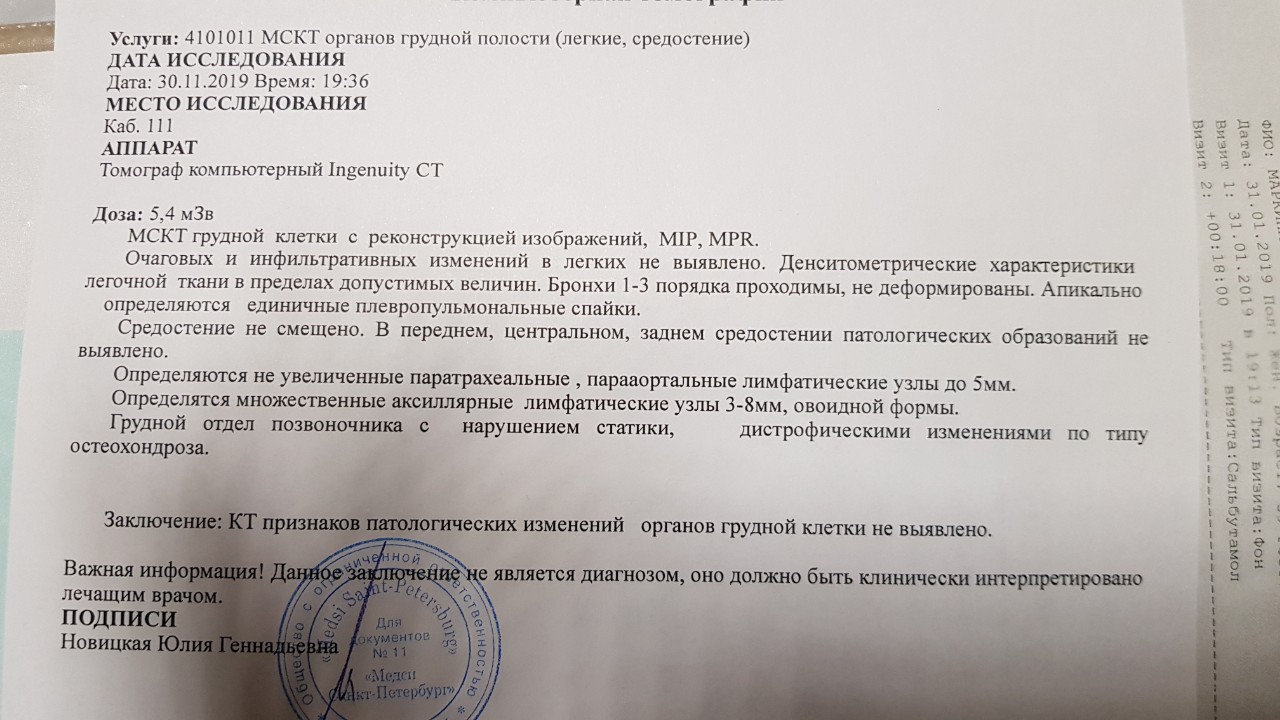

Фотографии и снимки КТ легких без контрастных веществ

Раздел: Визуальный дайджест